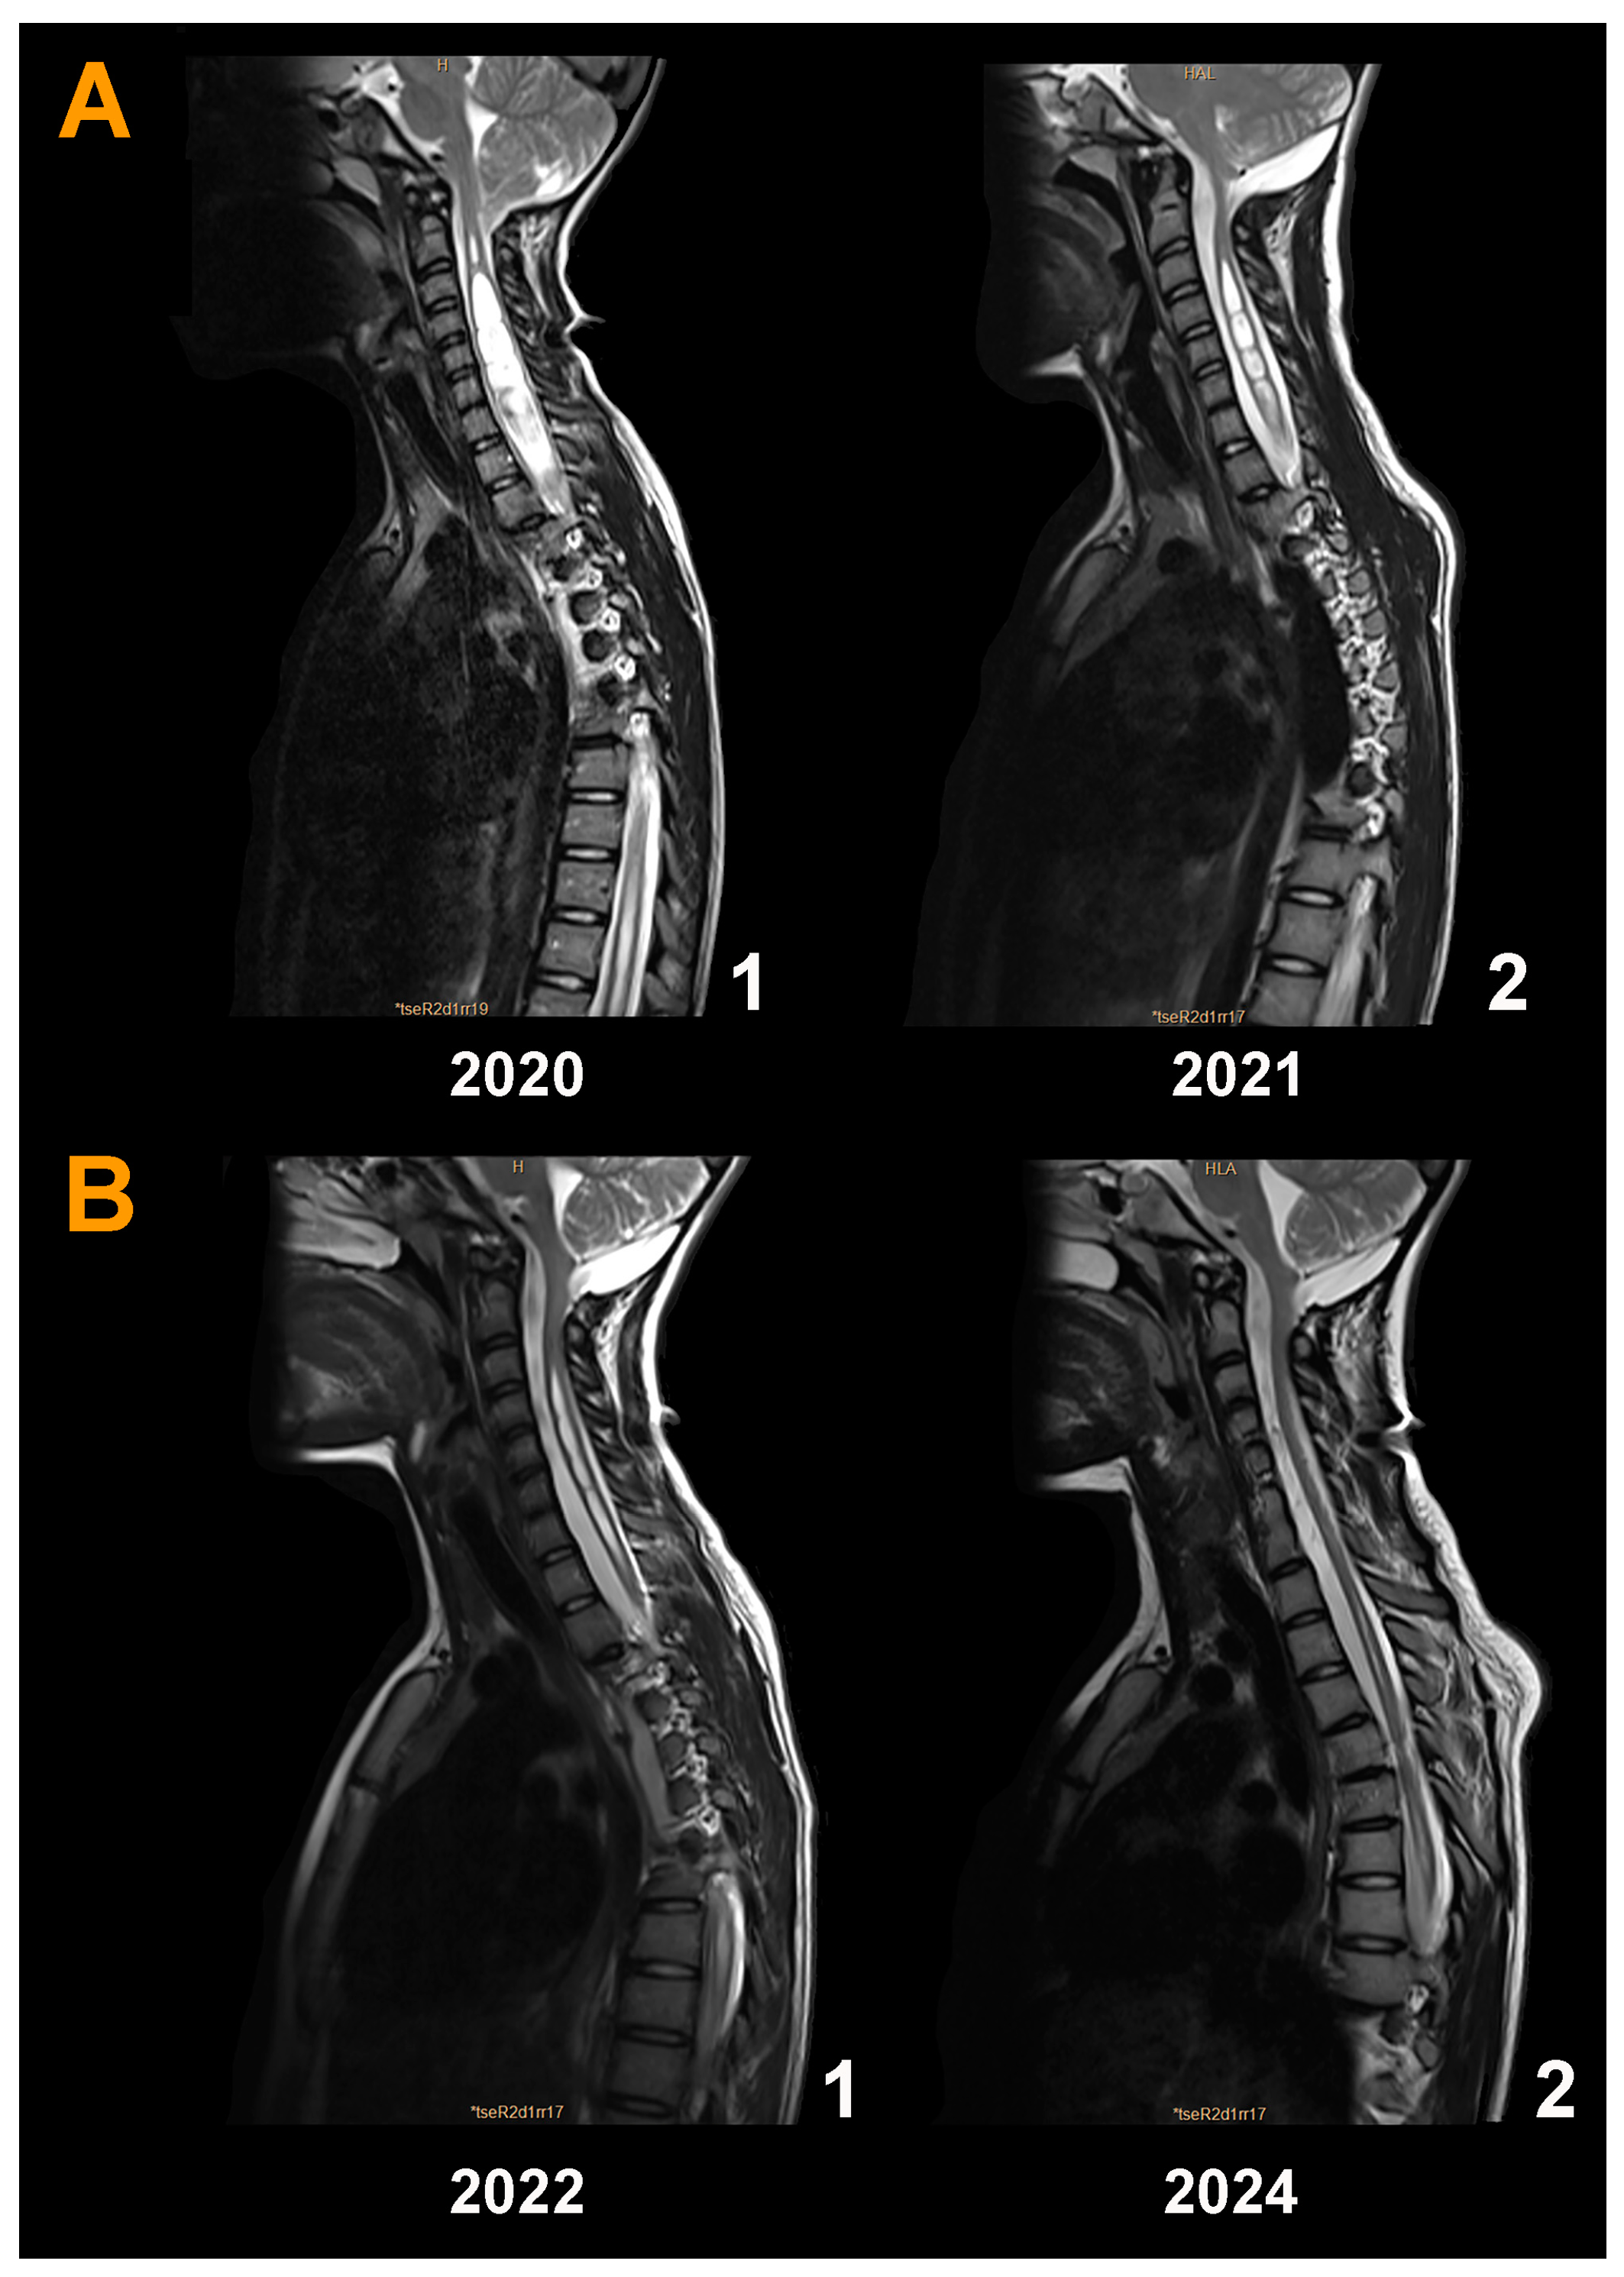

3.5. Neuroimaging Findings before and after Surgery